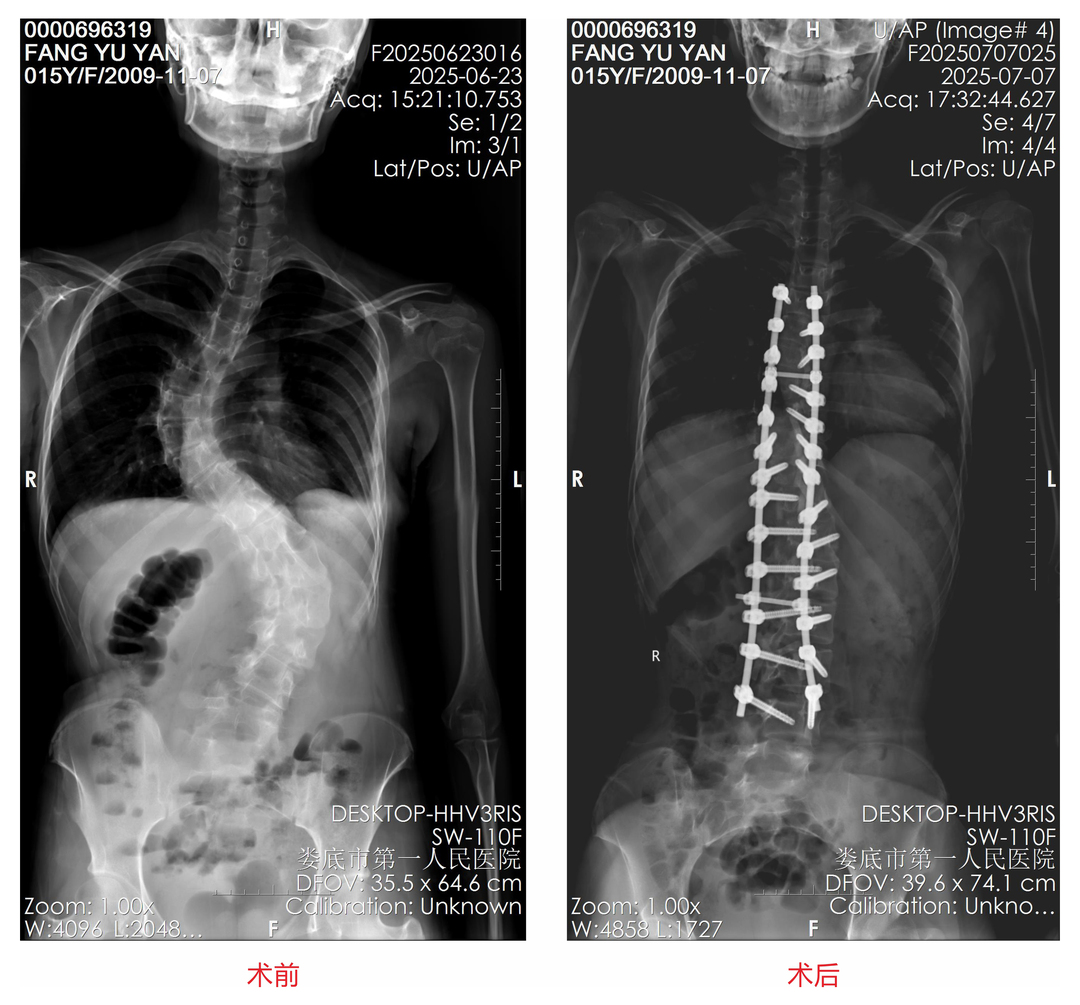

近日,随着中考结束,小方在家人的陪同下来到娄底市第一人民医院脊柱外科接受手术治疗。经医生详细查体,发现其胸弯及腰弯均达70°,整个脊柱呈"S"型,属于重度脊柱侧弯。

患者术前术后X片对比。

经过系统的术前评估,龙军华带领团队凭借丰富的手术经验,成功为小方实施了脊柱侧弯后路截骨矫形+植骨融合钉棒内固定术。